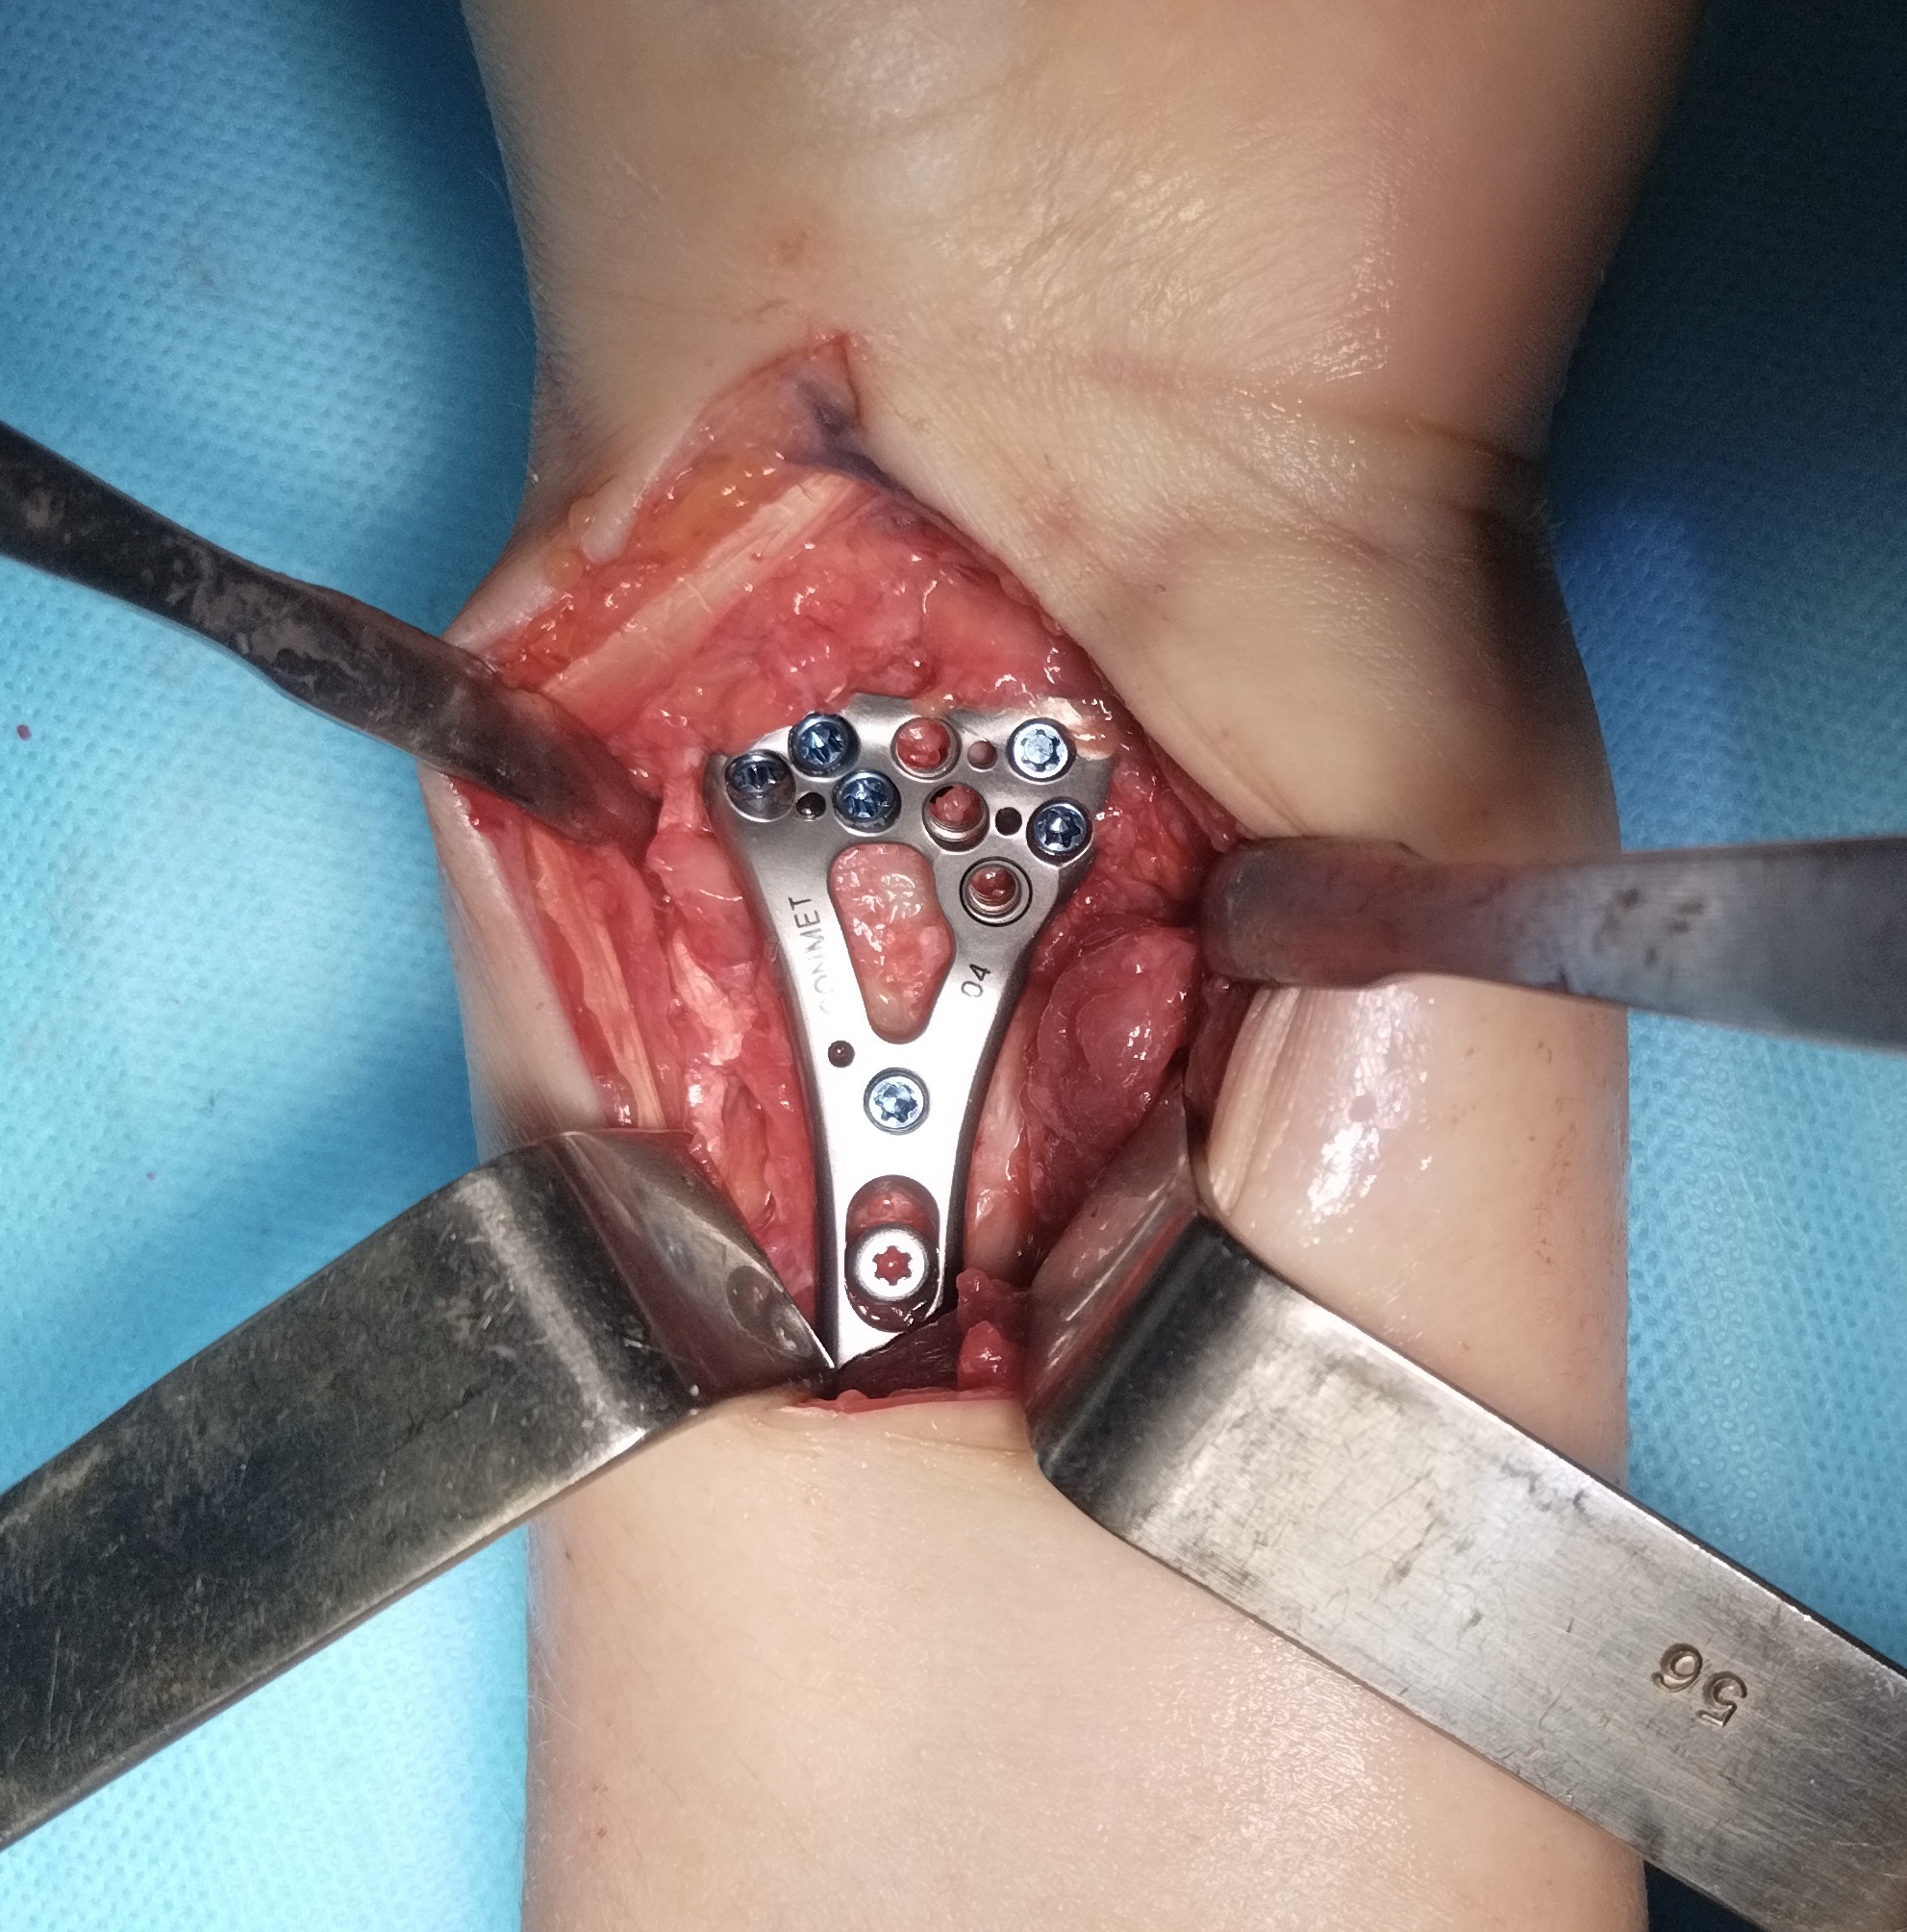

Клинический случай: внутрисуставной перелом дистального метаэпифиза лучевой кости — операция (остеосинтез пластиной)

Этап остеосинтеза: доступ, фиксация и контроль положения пластины.